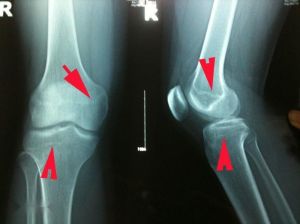

骨骺線先天性因素:(1)營養代謝障礙(維生素A、D過剩症);(2)骨折(外傷性、病理性);(3)放射性損傷;(4)骺板軟骨區感染(化膿性、結核性);(5)骺板軟骨燒傷、凍傷、創傷等;(6)大骨節病;(7)氟中毒;(8)小兒氟骨症。導致骨骺早閉的病因發生越早,畸形會越重,愈後也就越差。對國家、社會、家庭均帶來較重的經濟負擔,給患兒也會帶來一定的思想和精神壓力,。學者認為有些引起骺早閉的病因是完全可以避免的,有些病因雖能導致患兒致殘,但如果積極防治可降低致殘率的發生和減輕畸形。為此應注意以下幾個方面:

3、教育兒童加強自我保護避免各類創傷。骨關節跌傷後,應立即到有經驗的骨傷科(矯形外科)去整復治療,以免延誤診治,造成嚴重骨骺早閉畸形。

4、對一些導致骨骺早閉的地方病,意外事故、車禍、燒傷、凍傷等均應進行有針對性的積極防治,儘可能將畸形減少到最低程度。

目前各種骨骺早閉畸形肌體可以進行手術矯正及整形,使殘疾關節與畸形肌體功能得到部分恢復和改善。